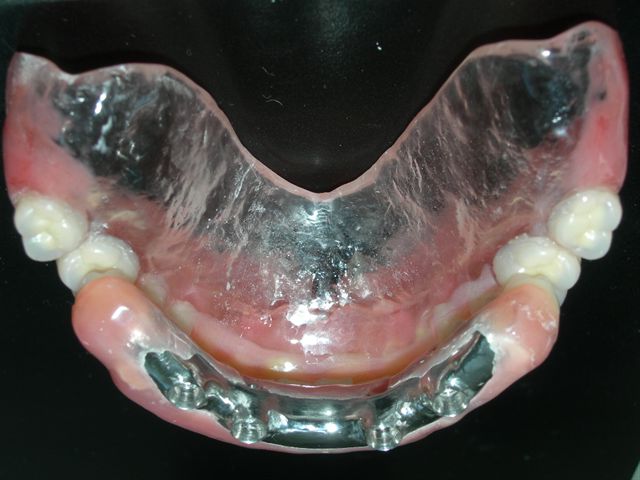

Protocolo acrilizada (VISTA SUPERIOR) |

Protocolo acrilizada (VISTA INFERIOR) |

| Seqüência cronológica laboratorial: 1) Fase de construção da barra protocolo com cera e componentes calcináveis e 2) Acrilização final |